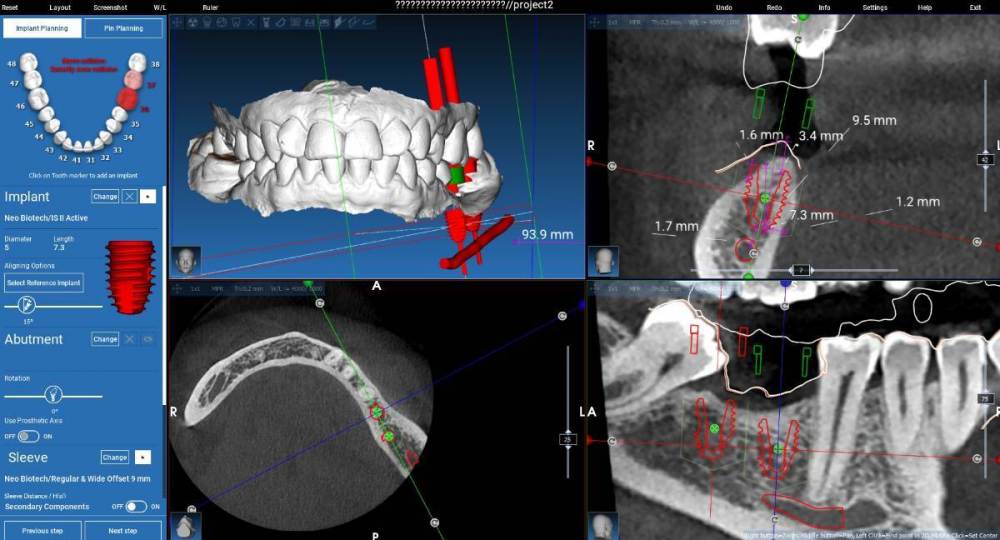

Fin Опубликовано 23 августа, 2023 Автор Поделиться Опубликовано 23 августа, 2023 21.08.2023 в 22:07, stommm сказал: Я нео не работал, но в каталоге видел с 5.0 с шекой 2.3. Попробуйте его нарисовать в планировщике и посмотрите как встанет 21.08.2023 в 21:06, TIGER сказал: @Fin регулярно ставлю 4 и 6 мм ,никаких проблем В моем случае поставили бы два 6мм штраумана? 21.08.2023 в 15:47, koreandr сказал: Так точно) Здравствуйте коллеги. Спасибо за ваши ответы. В планировщике, к сожалению нет импланта 5х7.3 с полировкой но по сути длина такая же. При планировании у пациентки получается перекрестный прикус- так и есть. Подгрузил прикус и немного поправил. Ссылка на комментарий

Fin Опубликовано 23 августа, 2023 Автор Поделиться Опубликовано 23 августа, 2023 5 часов назад, stommm сказал: Попробуйте вестибулярнее нарисовать и поставить. проще с с десной потом работать будет.в области нижних 7 особенно актуально. Несколько таких кецсов с проблемами. Вестибулярно все супер, а язычно нарастить не удаётся или плохо удаётся. Язык давит Имеете ввиду так? Всю кератинизированную слизистую придется смещать язычно. СДТ с апикальном смещением вестибулярно. Ссылка на комментарий